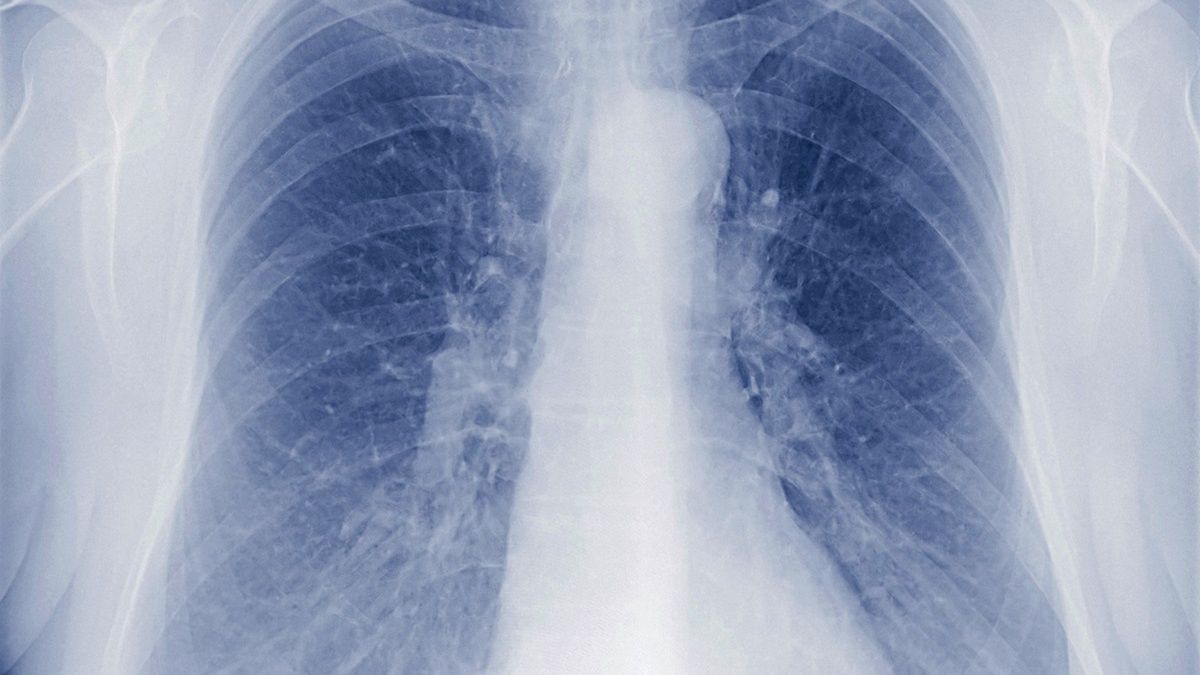

Lekarze z Włoch i Chin alarmują o problemie, który dotyka wielu ozdrowieńców po koronawirusie. COVID-19 może długotrwale uszkodzić organy wewnętrzne pacjentów, nawet jeśli przebyli jedynie łagodną formę choroby. Najbardziej zagrożone są płuca.

Koronawirus może trwale uszkodzić organy wewnętrzne pacjenta. Coraz więcej osób, które pokonały chorobę COVID-19, zmaga się teraz z "pokoronawirusowymi" problemami zdrowotnymi. Zwłaszcza w Chinach i we Włoszech lekarze obawiają się, że na razie widać jedynie wierzchołek góry lodowej pandemii.

W wielu przypadkach COVID-19 powoduje trwałe uszkodzenia narządów wewnętrznych, m.in. serca, wątroby lub płuc. Profesor Pedretti obawia się zwłaszcza masowych problemów z płucami.

W chińskim Wuhan lekarze wykryli oznaki zwłóknienia płuc nawet u pacjentów, którzy przeszli bezobjawową formę COVID-19. W artykule opublikowanym w czasopiśmie naukowym "The Lancet" podkreślili jednak, że nie wiadomo jeszcze, czy wykryte uszkodzenia płuc są nieodwracalne.

U niektórych ozdrowiałych pacjentów odnotowano spadek wydolności płuc o około 20-30 procent - przyznaje dr Owen Tsang Tak-yin, dyrektor Infectious Disease Centre at Princess Margaret Hospital w Hongkongu, cytowany przez The South China Morning Post.